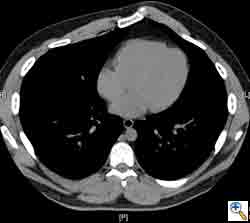

Here we present, as a paradigm of repair, the case of a 65 year old gentleman referred to our institution for an indolent mass in the left anterior chest wall. Repairs for other conditions follow the same rules. This mass had been stable in size for more than 12 months and the patient was prompted to seek medical attention as, after weight loss due to dieting, he felt the mass was uncomfortable while sleeping. Apart from coronary stenting for angina, the past medical history was unremarkable.

Computed tomography scan of the chest showed a mass protruding from the cortex of the third rib. A percutaneous core biopsy was non-diagnostic. We proceeded to an open incisional biopsy. This was reported as showing a spindle cell neoplasm. The patient was therefore scheduled, after multidisciplinary meeting discussion, for radical surgery.

At surgery, the mass was arising from the cortex of the third rib, and solid measuring 5x8 cm. There was no macroscopic involvement of the surrounding extra-thoracic musculature or of the underlying lung, the mass being confined to the rib and intercostal muscles. The patient underwent resection of the second to fourth ribs and the rhomboid muscle as well, in the attempt to get clear margin. The large antero-lateral defect was eventually reconstructed using 2 mouldable titanium bars. To prevent lung herniation through the defect, we reconstructed the layers anatomically using a biological patch (Veritas®). The final histopathology was a low grade sarcoma of the chest wall with clear resection margins.

He made an excellent recovery with daily physiotherapy to encourage shoulder movements. He was discharged with oral analgesia on postoperative day 4. At 1-month follow-up the patient had no pain at all, discontinued analgesia on postoperative day 17 and demonstrated a full range of shoulder movement. His chest x-ray was unremarkable and the wound healed without complication.